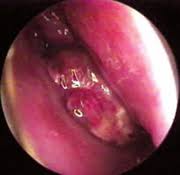

The CO2 and Nd:YAG lasers are used to shrink or destroy tumors. They can be used with thin, flexible tubes called endoscopes that let doctors see and work inside certain parts of the body that could not be reached except by major surgery. Using an endoscope also helps the laser beam accurately hit its target.

In the medical fields,Lasers are used this way to treat many kinds of cancer. Here are some examples:

•In certain cases, small cancers of the head and neck may be treated with lasers.